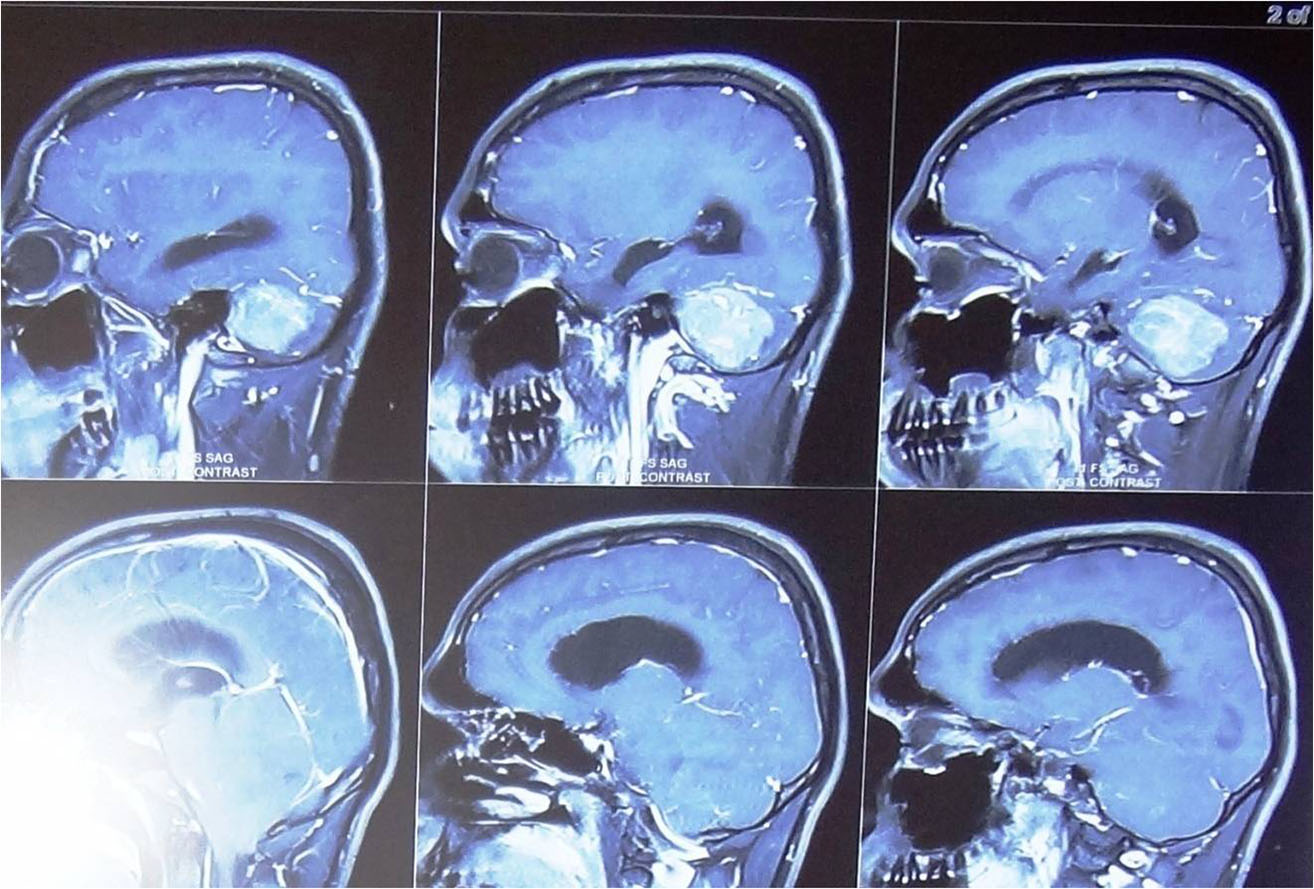

any of these symptoms he/ she should consult a neurosurgeon immediately. Usually CT Scan/ MRI of brain help

in the diagnosis. Most of the brain tumours can be safely treated by surgery but the treatment plan may vary